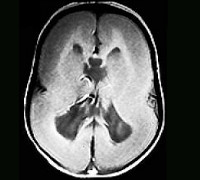

Опытные врачи и исследователи на протяжении последних десятилетий изучают эту редкую патологию и пытаются найти способы для лучшего понимания и лечения этого состояния. Благодаря современным методам диагностики, таким как магнитно-резонансная томография (МРТ), специалисты смогли изучить мозг детей с лиссэнцефалией и раскрыть некоторые аспекты его развития.

Диагностика лиссэнцефалии обычно основана на сочетании клинических признаков, результатов нейровизуализации и генетических исследований. Нейрологический осмотр может выявить отставание в развитии моторики, замедленную реакцию на звуки и свет, а также атипичные движения. Важную роль в диагностике играют данные нейровизуализации, такие как магнитно-резонансная томография (МРТ) и электроэнцефалограмма (ЭЭГ).

- МРТ: МРТ позволяет визуализировать структуру и анатомию мозга, исследуя его слоистую структуру и наличие извилин и борозд. У пациентов с лиссэнцефалией на МРТ обычно видно отсутствие или минимальное наличие извилин, а также утолщение коры мозга.